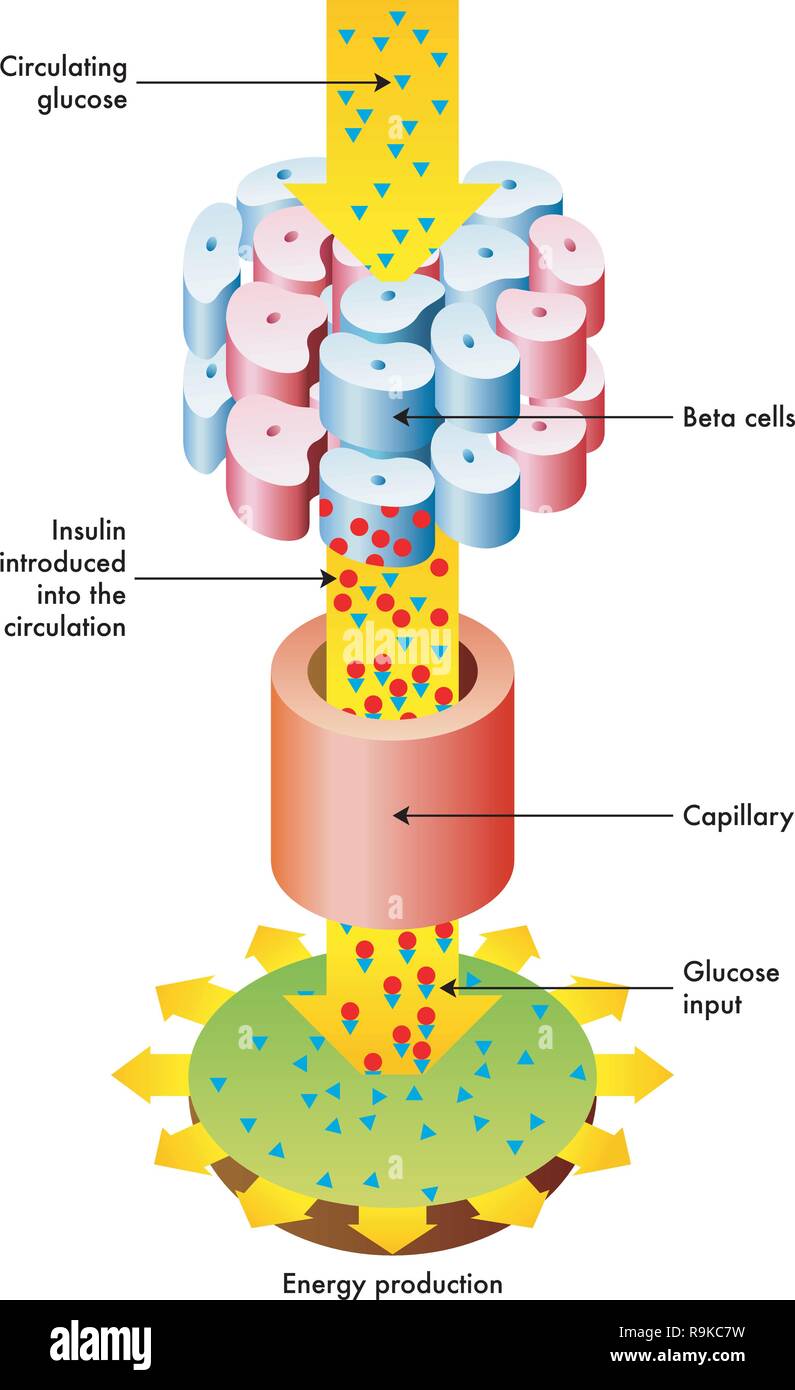

RFR9KC7W–Une illustration vectorielle médical de la libération d'insuline et la fonction dans le métabolisme.